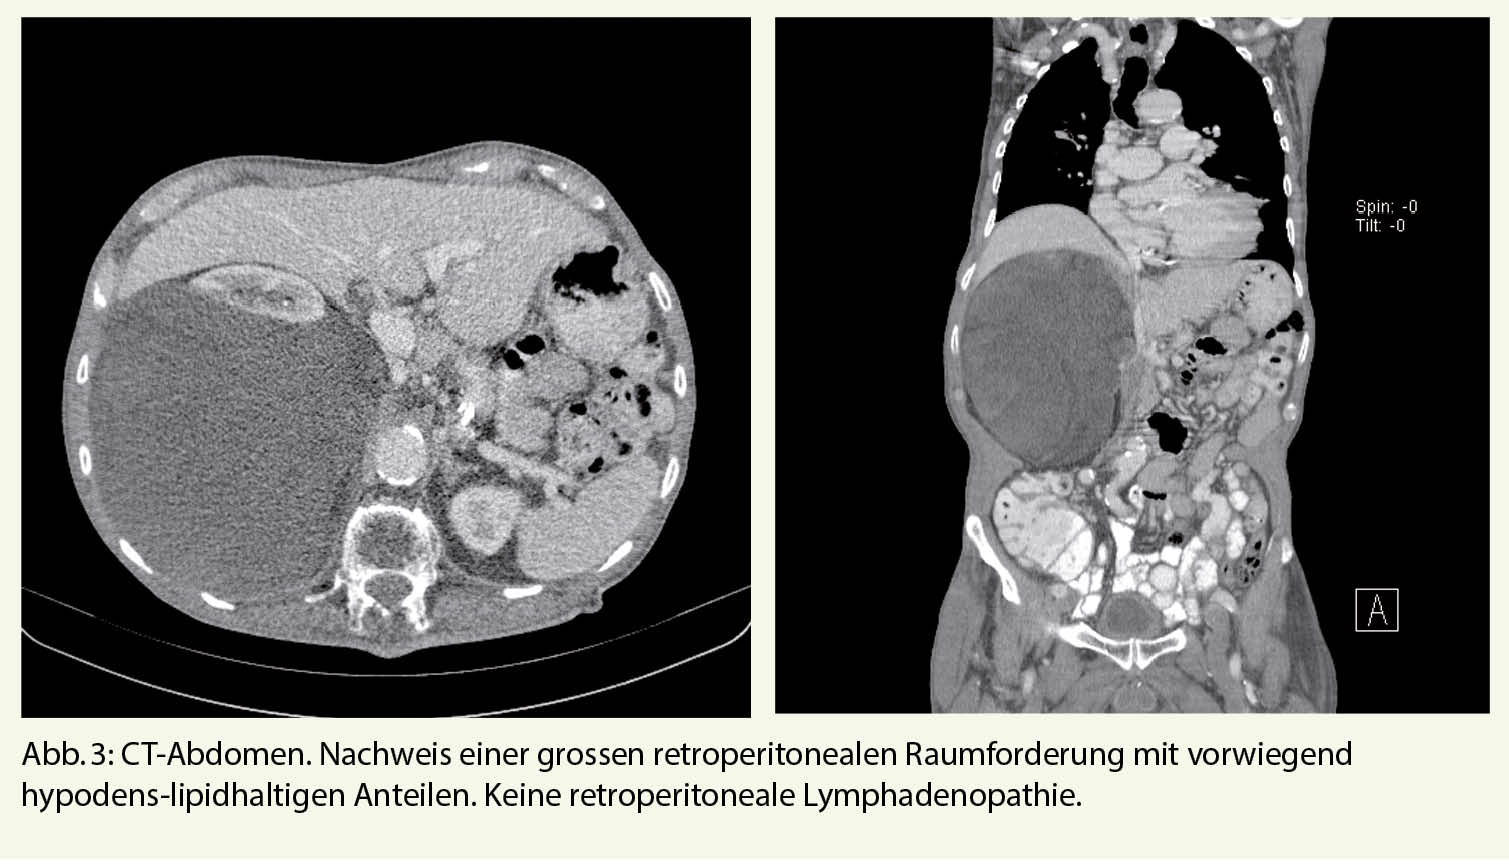

Klinisch zeigte sich eine glatte, rundliche, nicht druckdolente tumoröse Struktur im proximalen, posterioren Unterschenkel sowie eine Fussheberparese der ipsilateralen Seite. Die restliche klinische Untersuchung blieb bland. Angaben zur persönlichen Anamnese im Kasten. In der MRT-Untersuchung des linken Unterschenkels zeigte sich eine Raumforderung im postero-lateralen Muskelkompartiment in unmittelbarer Nachbarschaft zum N. peroneus (Abb. 1). Eine invasive Abklärung in Form von Biopsien hat der Patient abgelehnt. Zu den weiteren Nachkontrollen beim Hausarzt kam der Patient nicht mehr.

In unserem Fall hatte der Tumor bereits bei der ersten MRI Untersuchung eine Grösse > 5cm und eine Lage unmittelbar unterhalb der Muskelfaszien. Ausserdem konnte ein Wachstum dokumentiert werden. Aufgrund dieser Faktoren war eine Abklärung der Dignität mittels Core Nadel Biopsie (der heutige Standard) indiziert.

• Liposarkome im Frühstadium weisen im CT oder MRI keine typischen Malignitätszeichen auf wie Kontrastmittelanreicherung oder lokale Invasion und könnten als «benigne» missdeutet werden. Die Indikation zur ergänzenden Biopsie soll grosszügig gestellt werden.